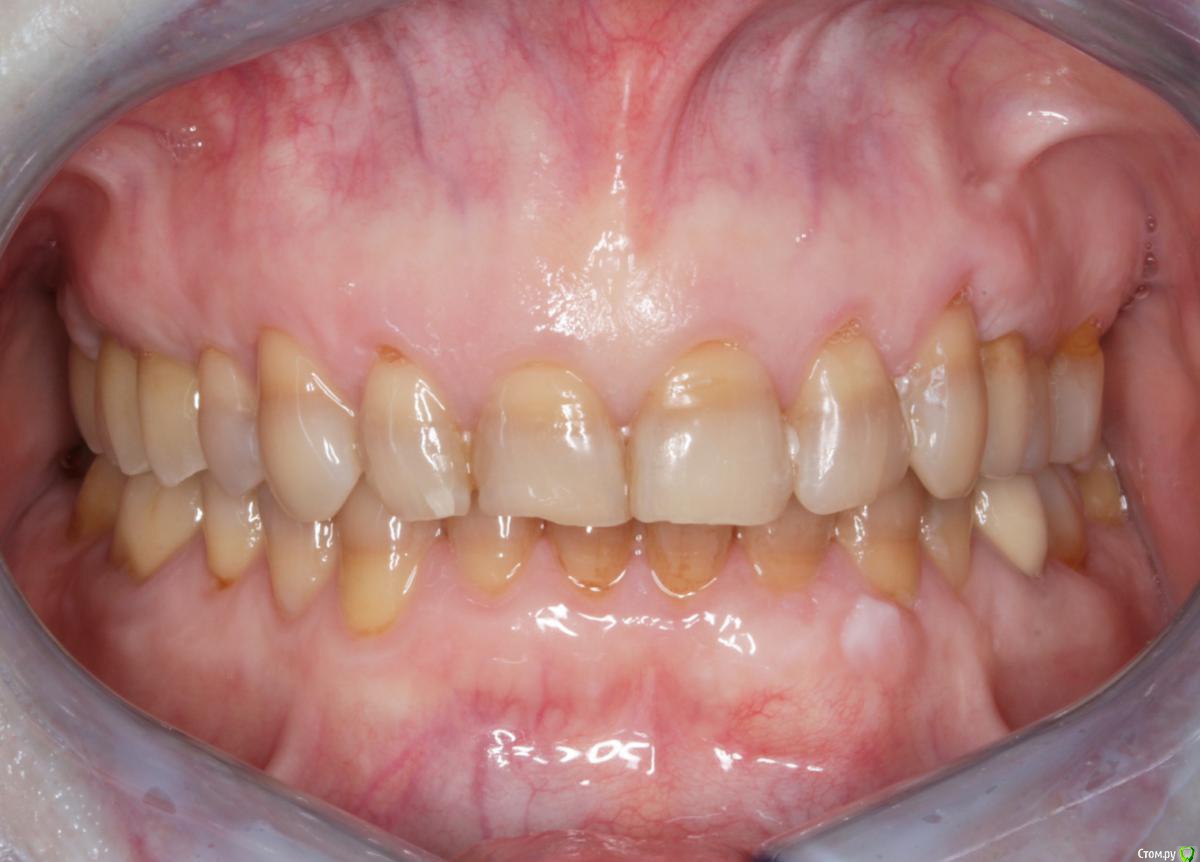

Пациентка пришла с целью восстановления отсутствующих 15,16,17,24,27 з.

Из анамнеза - хронический двухсторонний синусит, соответствующие зубы удалены более 5-ти лет назад, тетрациклиновые зубы ( от изменения цвета отказалась ).